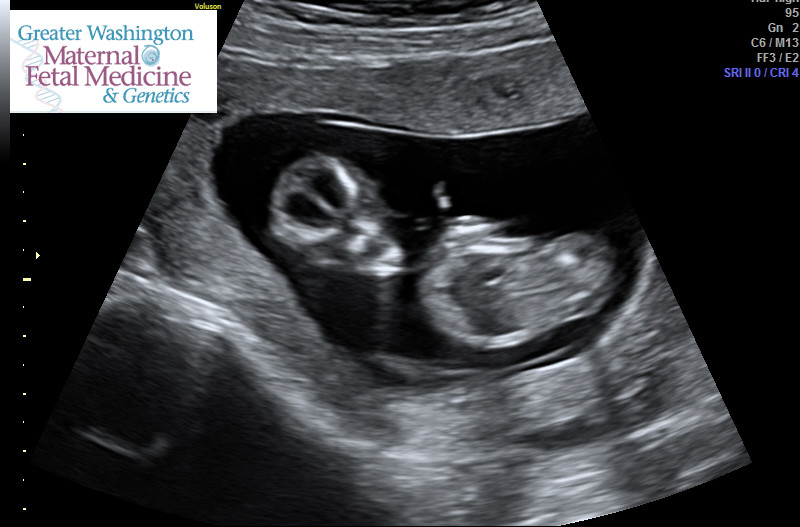

Three beautiful boys and my longed-for DD due in June 2016!